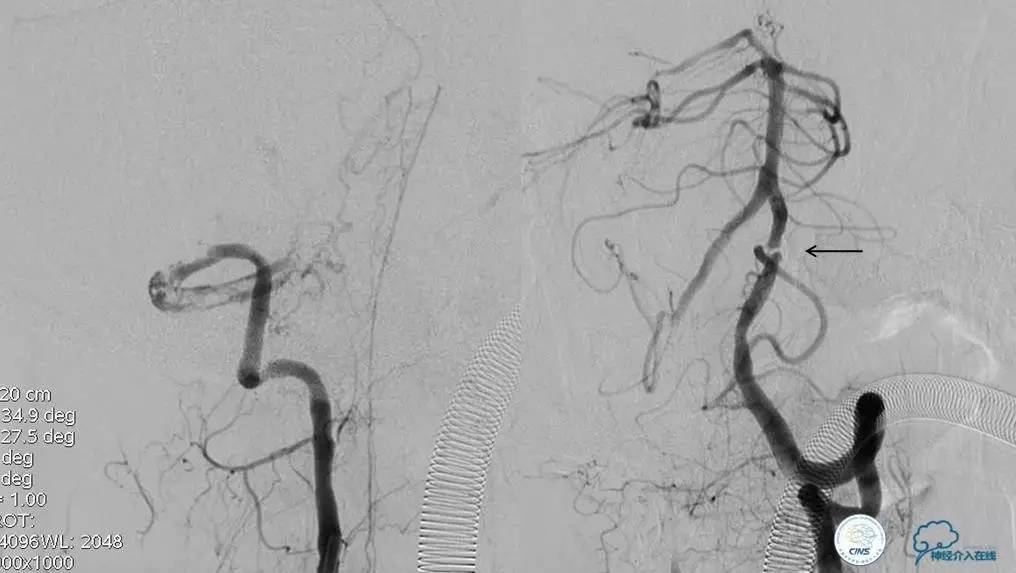

术前DSA

▼2013-12-13

▼2013-12-27

术后仍残余部分狭窄,但头晕明显缓解。